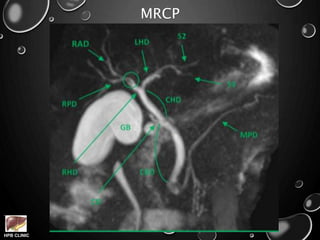

MRCP

• CT volumetry, CT angiography, MRCP